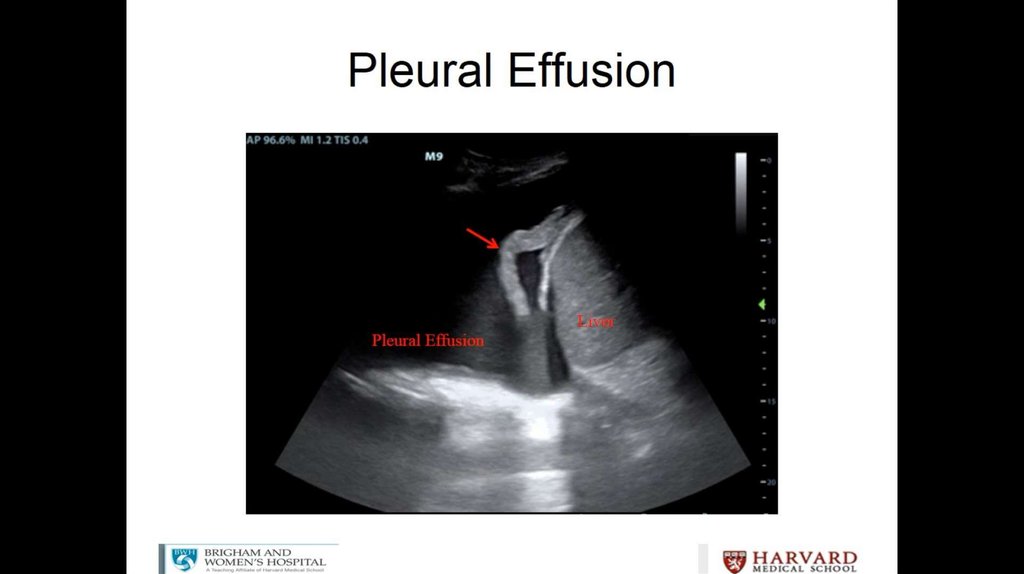

Litrasound in the ICU: What Every Intensivist Should Know